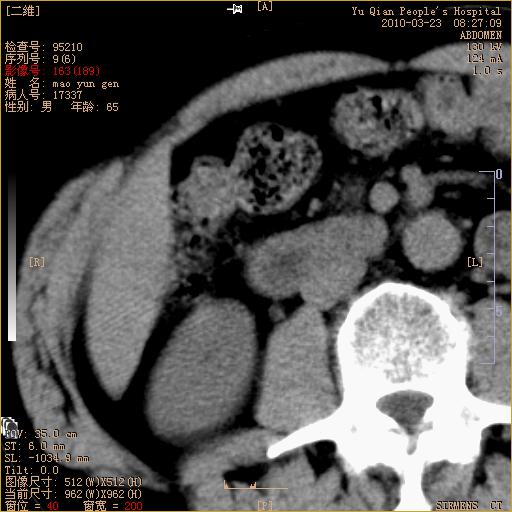

标题: CT25266:消瘦月余,前来肝部检查,请看看肠腔 [打印本页]

标题: CT25266:消瘦月余,前来肝部检查,请看看肠腔

肝区结肠占位,腺癌可考虑,建议肠镜活检。

升结肠肠壁增厚,不均强化,考虑升结肠腺癌可能性,建议肠镜检查。

1)考虑升结肠癌。2)右肾小囊肿。